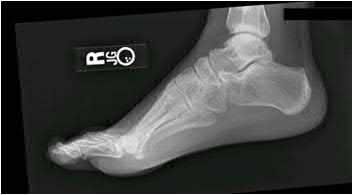

A 40-year-old male sustains a high-energy Pilon fracture. Initial treatment consists of a spanning external fixator across the ankle joint. Which of the following clinical findings best indicates that the soft tissue envelope has recovered sufficiently to permit definitive open reduction and internal fixation (ORIF)?

Correct Answer: Return of the 'wrinkle sign' on the anterior ankle skin

Explanation:

In the staged management of high-energy Pilon fractures, definitive ORIF must be delayed until the soft tissue envelope has adequately healed to minimize the risk of wound complications and infection. The return of skin wrinkles (the 'wrinkle sign') indicates a significant reduction in interstitial edema and is the widely accepted clinical milestone for proceeding with definitive fixation, typically 10 to 21 days post-injury.